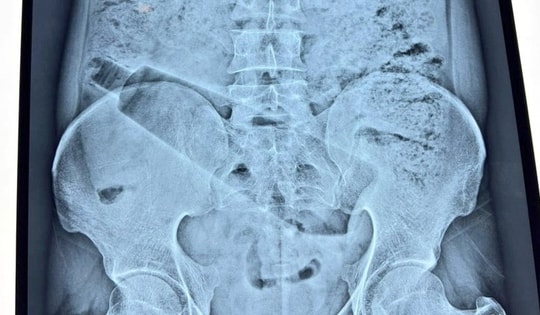

Người phụ nữ 67 tuổi ở Bắc Ninh xuất hiện cảm giác đau tức bụng trong nhiều ngày nên đã đến bệnh viện thăm khám. Bác sĩ phát điều bất thường trong bụng bà, ước tính nặng gần 1 kg.